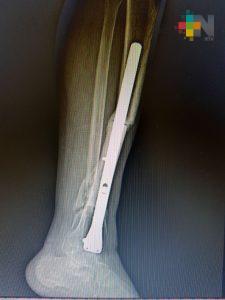

Xalapa, Ver.- Un equipo médico multidisciplinario del Instituto Mexicano del Seguro Social (IMSS) en Veracruz restituyó 11 centímetros de hueso de la pierna de un hombre que sufrió un accidente, mediante el trasplante de tejido óseo cadavérico que le permitió conservar la extremidad y volver a caminar.

El hueso implantado se obtuvo del Banco de Tejidos en el Estado de México a solicitud expresa de los médicos tratantes. El injerto fue realizado en el Hospital General de Zona No. 11 «Ignacio García Téllez», de la ciudad de Xalapa.

Luis René transitaba en su motocicleta cuando fue arrollado por un vehículo y, como resultado del accidente, perdió una tercera parte de la tibia y el peroné de la extremidad izquierda.

Fue aproximadamente una pérdida de 11 centímetros de hueso, por lo que al llegar al hospital se le realizaron cirugías para preservar la viabilidad de los tejidos afectados y la colocación de placas en las partes óseas.

Por la fractura expuesta, la fragmentación de los huesos y debido a que la pierna estaba unida al tobillo sólo por tejido blando, un procedimiento inmediato era la amputación, explicó el especialista en Traumatología y Ortopedia del Hospital General de Zona No. 11, Eduardo Morales Martínez, quien encabezó al equipo multidisciplinario que atendió a Luis René.

Sin embargo, se buscó la forma de salvar el miembro y mediante la recuperación de la viabilidad de los tejidos blandos se optó por el implante óseo. El doctor Morales explicó que en este caso se activó el protocolo para solicitar tejido óseo y al cabo de algunos meses se logró obtener el hueso de un cadáver apto para implantarse.

Fue necesario recurrir a un implante de hueso porque era una lesión muy extensa. No había sustento, no había hueso, no había de dónde fijar la placa. Era prácticamente una pérdida total, el pie estaba suelto y no había soporte que uniera esas dos estructuras, explicó el especialista. El riesgo de pérdida de la extremidad fue alto y el proceso de recuperación fue de aproximadamente un año.

Detalló que actualmente Luis está totalmente recuperado, es capaz de caminar sin asistencia, puede apoyarse sin soporte, es independiente para todas sus actividades y lo más importante, es que preservó su pierna.

La recuperación del hueso está al 100, ya tiene una integración radiográfica del injerto y debe continuar con el ejercicio de deambulación, puntualizó.